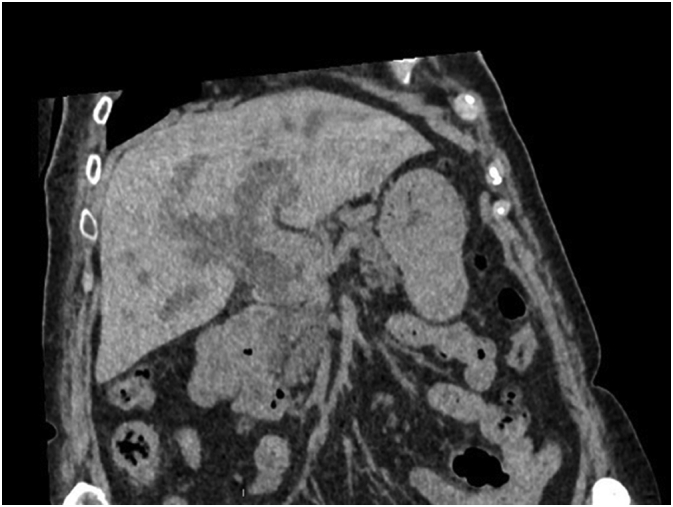

Because of an acute renal failure due to hyperbilirubinemy, a non-contrast-enhanced CT scan was performed. This exam confirms an irregular dilatation of intrahepatic biliary tree with an obstruction in the distal part of common bile duct associated with pathologic local lymph nodes and a suspect lesion of segment IVb of the liver (Fig. 1).